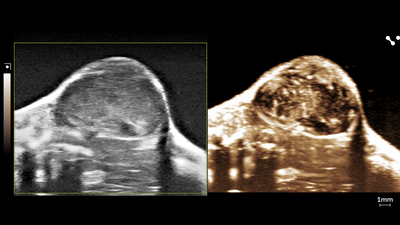

Perfusion in Tumor

High-resolution ultrasound (left) and nonlinear contrast (right) image of a subcutaneous tumor showing perfusion in the tumor tissue.